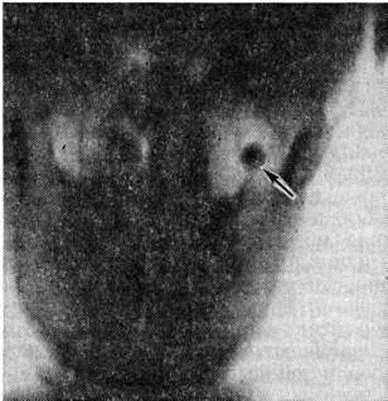

Рентгенологические исследование позволяет не только обнаружить Остеома, но и спреде лить её форму, структуру, положение, размеры и взаимоотношение с соседними органами. Компактная Остеома на рентгенограмме имеет форму округло-овальной интенсивной бесструктурной тени (рисунок 2). Губчатая

|